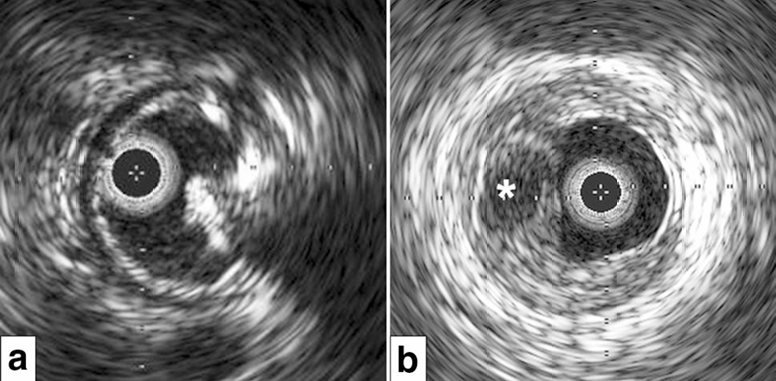

a、b. 内PIERCE技术示意图。图a显示,通过建立顺行入路部位与远端穿刺部位之间的导丝外置化,或通过顺行球囊导管在钙化病变近端锚定逆行导丝,实施远端BTK或BTA穿刺的双向入路。图b显示,从远端穿刺部位沿导丝将20G穿刺针置入动脉内,小心地边旋转边推进20G穿刺针,数次穿过钙化病变。

a–f. 器械输送困难的代表性病例。术前血管造影(a)显示胫后动脉(PTA)长段慢性完全闭塞(CTO)。图b显示,从PTA远端的逆行导丝穿过CTO病变并被外置化。低剖面球囊导管无法穿过钙化病变(虚线)。图c显示内PIERCE技术。图d显示低剖面球囊穿过并扩张钙化病变。图e显示通过长球囊导管实现充分的病变扩张。最终血管造影(f)显示PTA成功重建血运。